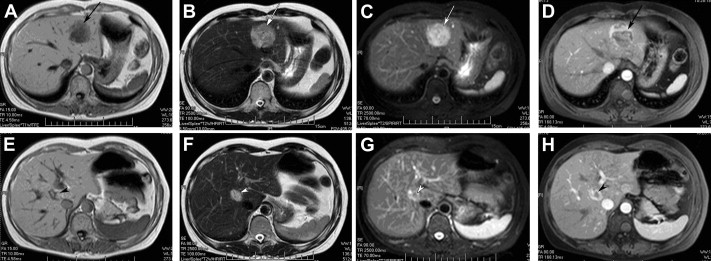

All patients received ultrasonography and computed tomography (CT) examinations, but only two patients received magnetic resonance imaging (MRI). On sonography, the tumors were seen as a hyperechoic mass, either homogeneous or heterogeneous. The lesions exhibited well-demarcated mass with heterogeneous density in plain CT scan. In arterial CT, the lesions were heterogeneously enhanced. In the portal venous phase, the lesions returned to an isoattenuating state (Fig. 1). In a 37-year-old woman complicated with renal PEComa, MRI showed heterogeneous hypointensity on T1-weighted images (T1WIs) and hyperintensity on T2-weigthed images (T2WI). After fat saturation, hyperintensity on T2WI in the liver lesion remained, but T2WI in the renal lesion showed hypointensity. In enhanced scanning, the lesions showed asymmetrical enhancement in arterial phase images (Fig. 2). In a 52-year-old woman with multiple liver lesions, MRI showed a lesion located on the left lobe and S8 of the liver. The lesions showed heterogeneous hypointensity on T1WI and heterogeneous hyperintensity on T2WI. After fat saturation, hyperintensity on T2WI remained. In enhanced scanning, the lesions showed asymmetrical enhancement in arterial phase images (Fig. 3). Prior to operation, one case was diagnosed with hepatic PEComa, three cases with hepatocellular carcinoma, and one case with hepatic adenomata.

CT image of hepatic PEComa. (A) Plain CT scan showed a well-demarcated mass with ...

Figure 1.

CT image of hepatic PEComa. (A) Plain CT scan showed a well-demarcated mass with heterogeneous density in the liver. (B) Contrast-enhanced CT scan of the same lesion showed a heterogeneously enhanced lesion in the arterial phase. (C) Contrast-enhanced CT scan of the same lesion showed the lesion returned to an isoattenuating state in the portal phase. CT = computed tomography.